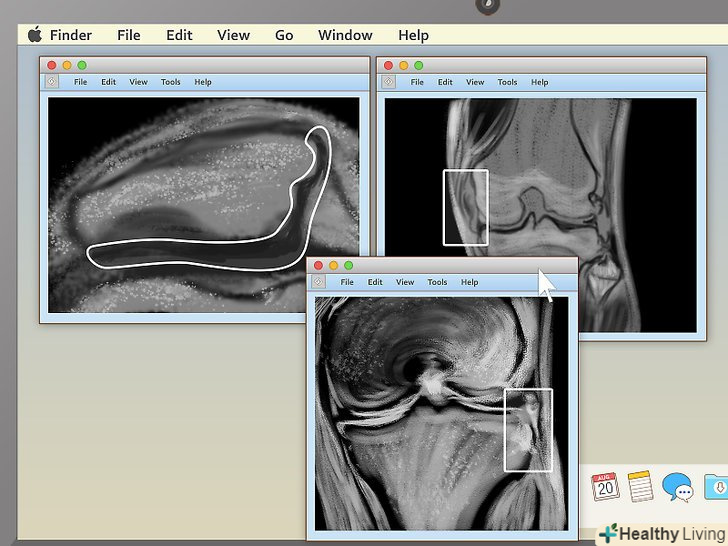

Якщо ви переглядаєте МРТ коліна, шукайте відмінності в знімках двох колінних чашок.Порівняйте знімок здорового коліна в корональній проекції зі знімком травмованого коліна, і ви знайдете проблему. МРТ коліна часто роблять для діагностики наступних захворювань і травм:[10]- Остеоартрит. На знімку відстань між суглобами буде менше, ніж повинно бути. Може бути помітно утворення кісткового наросту.

- Розрив зв'язок. На знімку відстань між суглобами буде більше, ніж повинно бути. Пазуха може наповнюватися рідиною, яка буде відображатися білим або світло-сірим. Може бути видно сам розрив.

- Розрив меніска. На знімку відстань між суглобами буде ненормальним. Будуть видні темні ділянки, спрямовані всередину, з будь-якого боку суглоба.